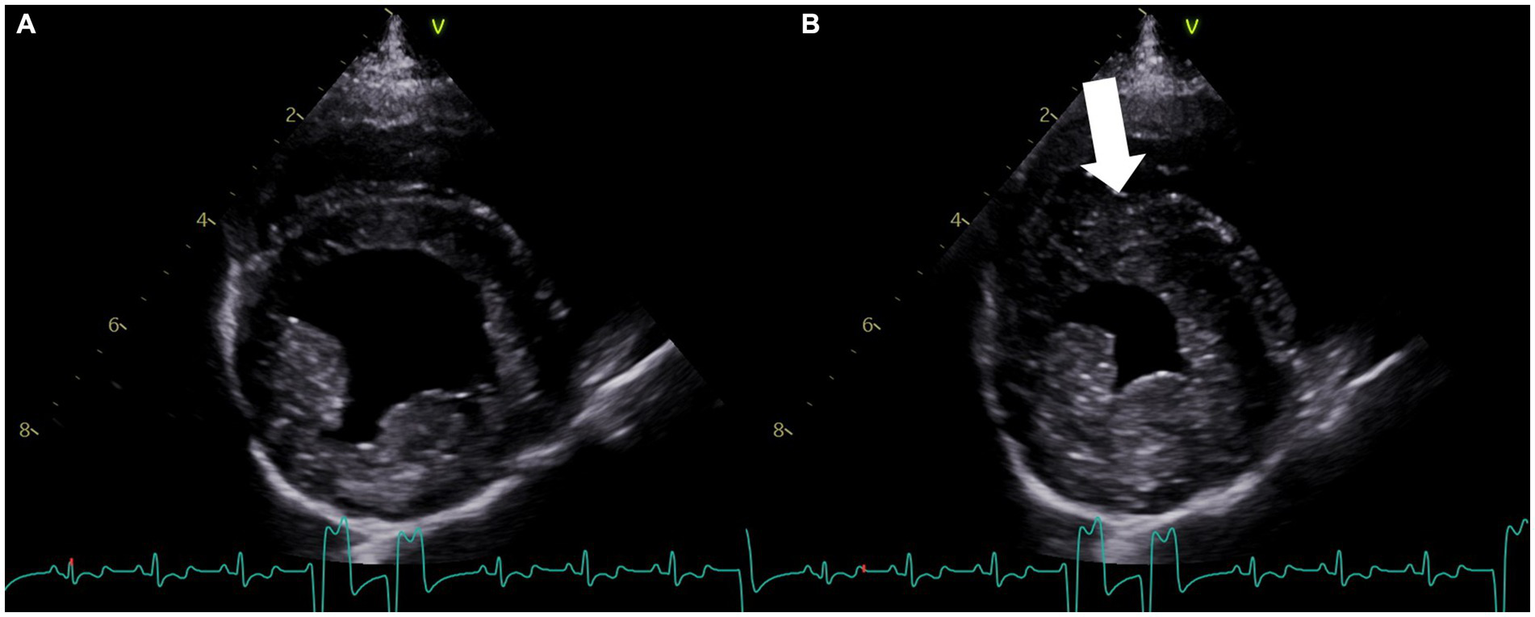

Figure 1. Right parasternal four-chamber short-axis echocardiogram image at the level of the left ventricle obtained on the second day of hospitalization. (A) View of the left ventricle in diastole. (B) View of the left ventricle during systole showing the dyskinetic motion of the interventricular septum (arrow). The concurrent lead II electrocardiogram shows ventricular tachycardia in both (A,B).

Later that night, the patient became hyperthermic (105.9°F/41.1°C). Ampicillin-sulbactam (30 mg/kg IV q8h) was prescribed due to concern for silent regurgitation and potential aspiration pneumonia. Initially, the patient’s temperature decreased, but it subsequently increased to 106°F (41.1°C). At this time, the heart rate had increased to 186 beats per minute, and facial focal epileptic seizures were noted. Levetiracetam (60 mg/kg IV) and midazolam (0.3 mg/kg IV) were administered. A lead II electrocardiogram was suspicious for ventricular tachycardia. Lidocaine (2 mg/kg IV, repeated twice) was given immediately followed by a lidocaine CRI at 30 mcg/kg/min, which was progressively increased over 3 h to 100 mcg/kg/min due to persistent ventricular arrhythmias. As the CRI rate increased, a total of eight additional lidocaine boluses (2 mg/kg each) were administered. Due to the lack of response, lidocaine was discontinued, and an amiodarone CRI (0.8 mg/kg/h) was started with minimal response. An echocardiogram identified focal dyskinesis (an outward motion of the wall during systole) of the inferoseptal and anteroseptal portions of the interventricular septum (Figure 1; Supplementary Video S1). Cardiac troponin I was markedly elevated (28.48 ng/mL, reference range: 0.00–0.05 ng/mL). A 10-lead electrocardiogram was performed and confirmed persistent ventricular tachycardia (Figure 2, heart rate 260 beats/min) with intermittent periods of accelerated idioventricular rhythm. Due to the presence of ventricular arrhythmias, focal dyskinesis, and a marked elevation in cardiac troponin I, NSM was suspected. Due to the poor response to amiodarone, it was discontinued, and two boluses of esmolol (50 mcg/kg/dose IV) were administered. During the second bolus, the patient was converted into a normal sinus rhythm with intermittent single ventricular premature complexes. An esmolol CRI was started and titrated to effect (10–20 mcg/kg/min). Dexamethasone (0.14 mg/kg IV q24h) was administered, and levetiracetam (30 mg/kg IV q8h) was continued.

In human medicine, echocardiography is used to diagnose and monitor left ventricular wall dysfunction in patients with neurologic insults and who are at risk for neurogenic cardiomyopathies (2, 1014). New myocardial dysfunction, characterized by global or regional wall abnormalities, such as hypokinesis or dyskinesis, is the primary criterion for the diagnosis of NSM (4). The patient described in this case study presented with status epilepticus, likely the inciting event for the development of NSM, and later developed arrhythmias. Electrocardiographic abnormalities are also common in patients with NSM (4), including in experimental dog models (15), and the arrhythmias in the dog in this report spurred the recommendation for echocardiography. The echocardiogram in this case confirmed the presence of a regional wall abnormality (dyskinesis, outward bulging of the ventricular myocardium during systole; Figure 2; Supplementary Video S1).